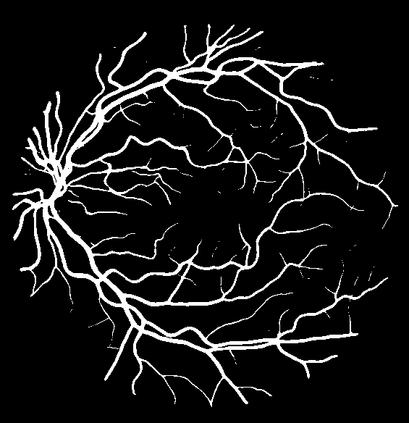

Blood vessel segmentation is crucial for many diagnostic and research applications. In recent years, CNN-based models have leaded to breakthroughs in the task of segmentation, however, such methods usually lose high-frequency information like object boundaries and subtle structures, which are vital to vessel segmentation. To tackle this issue, we propose Boundary Enhancement and Feature Denoising (BEFD) module to facilitate the network ability of extracting boundary information in semantic segmentation, which can be integrated into arbitrary encoder-decoder architecture in an end-to-end way. By introducing Sobel edge detector, the network is able to acquire additional edge prior, thus enhancing boundary in an unsupervised manner for medical image segmentation. In addition, we also utilize a denoising block to reduce the noise hidden in the low-level features. Experimental results on retinal vessel dataset and angiocarpy dataset demonstrate the superior performance of the new BEFD module.

翻译:近些年来,有线电视新闻网的模型导致分离任务突破,然而,这类方法通常会失去物体边界和对船只分割至关重要的微妙结构等高频信息;为解决这一问题,我们提议加强边界和地貌分解模块,以促进网络能力,在语义分解中提取边界信息,这种信息可以以端到端的方式纳入任意编码器-分解器结构。通过引入索贝尔边缘探测器,网络能够在之前获得更多边缘,从而以不受监督的方式加强医疗图像分解的边界。此外,我们还利用一个分解区块来减少低层特征中隐藏的噪音。关于再生容器数据集的实验结果和血管合成数据集显示了新的BEFD模块的优异性性表现。